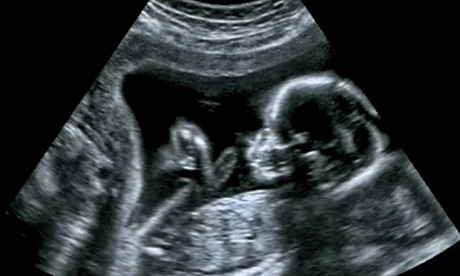

Under the Choice of Termination of Pregnancy Act of 1996, abortions are legal up to 12 weeks of pregnancy.

In pregnancies as a result of rape, incest or in cases of financial hardship, abortions are legal up to 20 weeks.